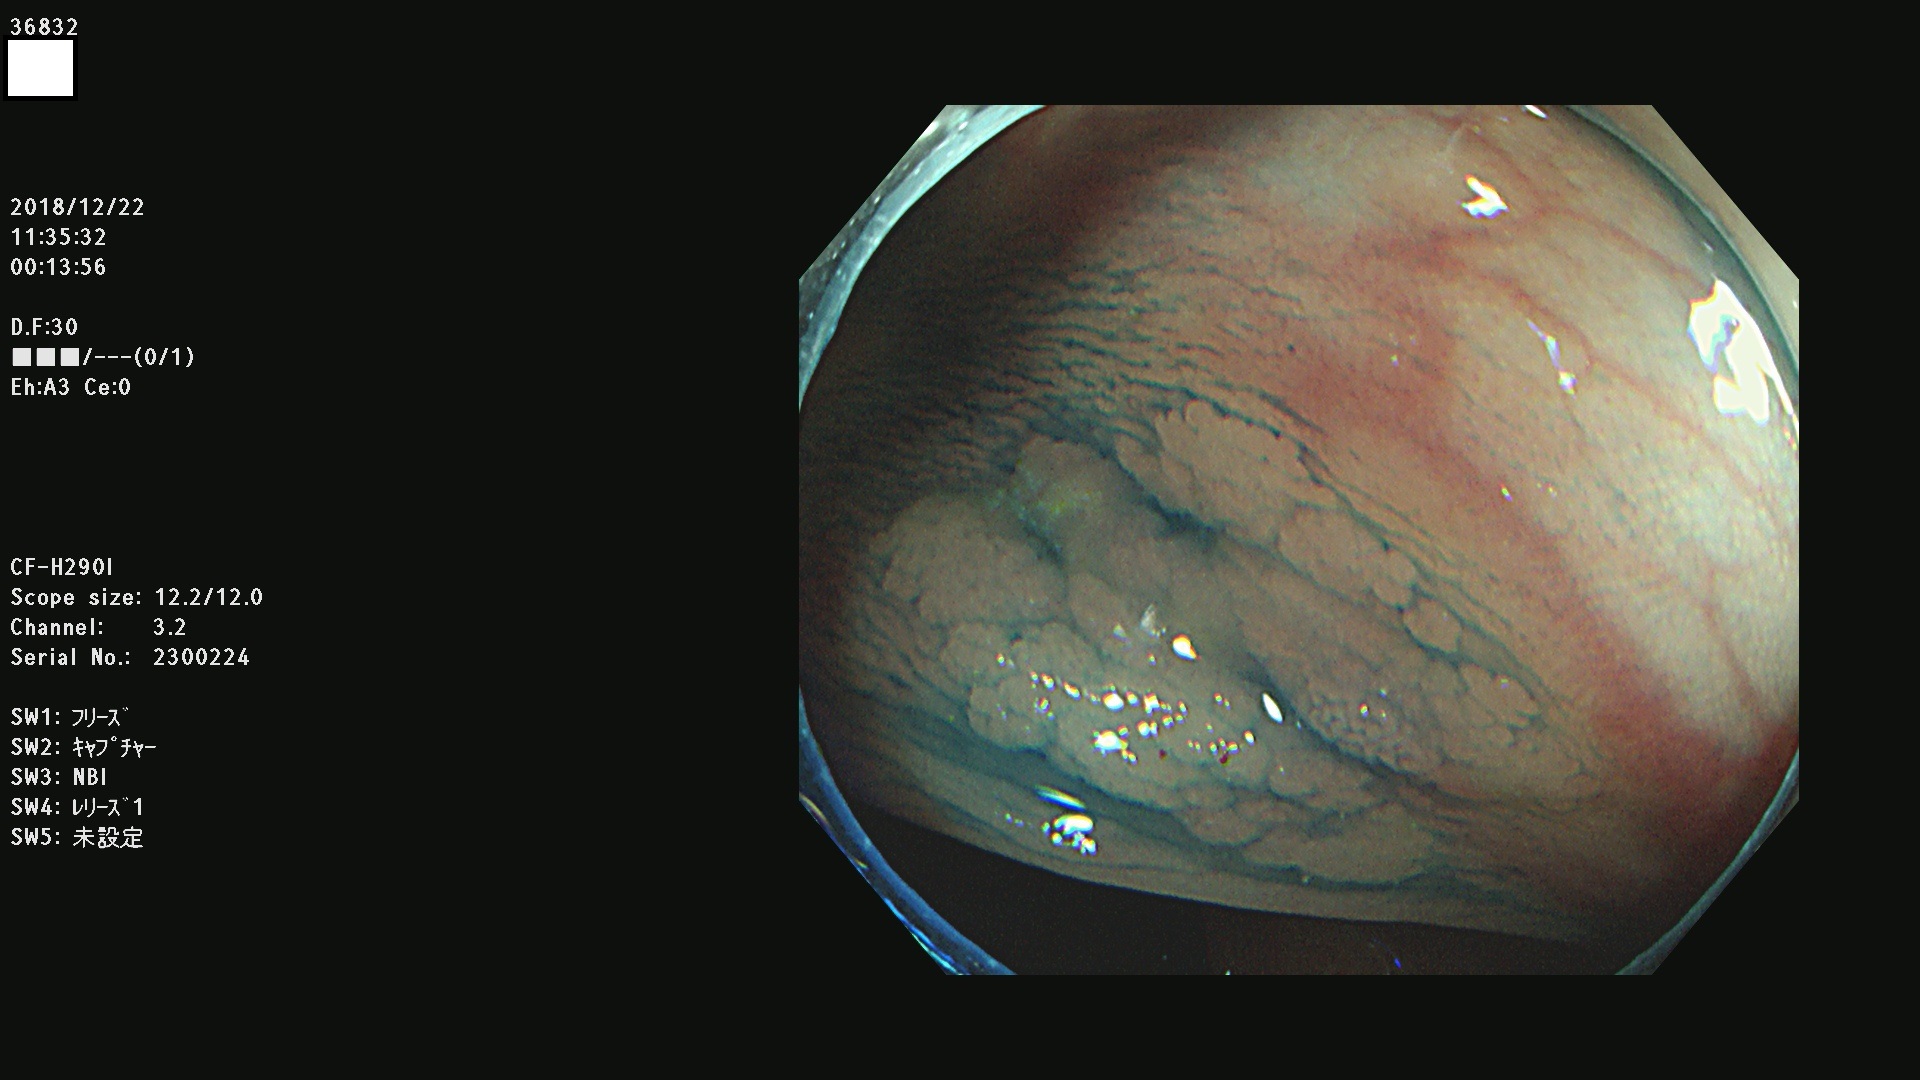

発見困難で危険性の高い平坦型病変(上記100名より抽出)

36804 36806 36807 36808 36809 36810 36811 36813 36815 36816 36817 36818 36820 36821 36822 36824 36825 36826 36828 36829 36830 36831 36832 36833 36834 36835 36837 36840 36841 36842 36845 36846 36848 36849 36851 36852 36853 36854 36855 36857 36859 36860 36861 36862(SSAPのみ) 36863 36864 36866 36868 36869 36870 36873 36875 36877 36878 36879 36881 36882 36883 36884 36885 36886 36887 36888 36889 36891 36892 36893 36894 36895 36896 36897 36898 36899